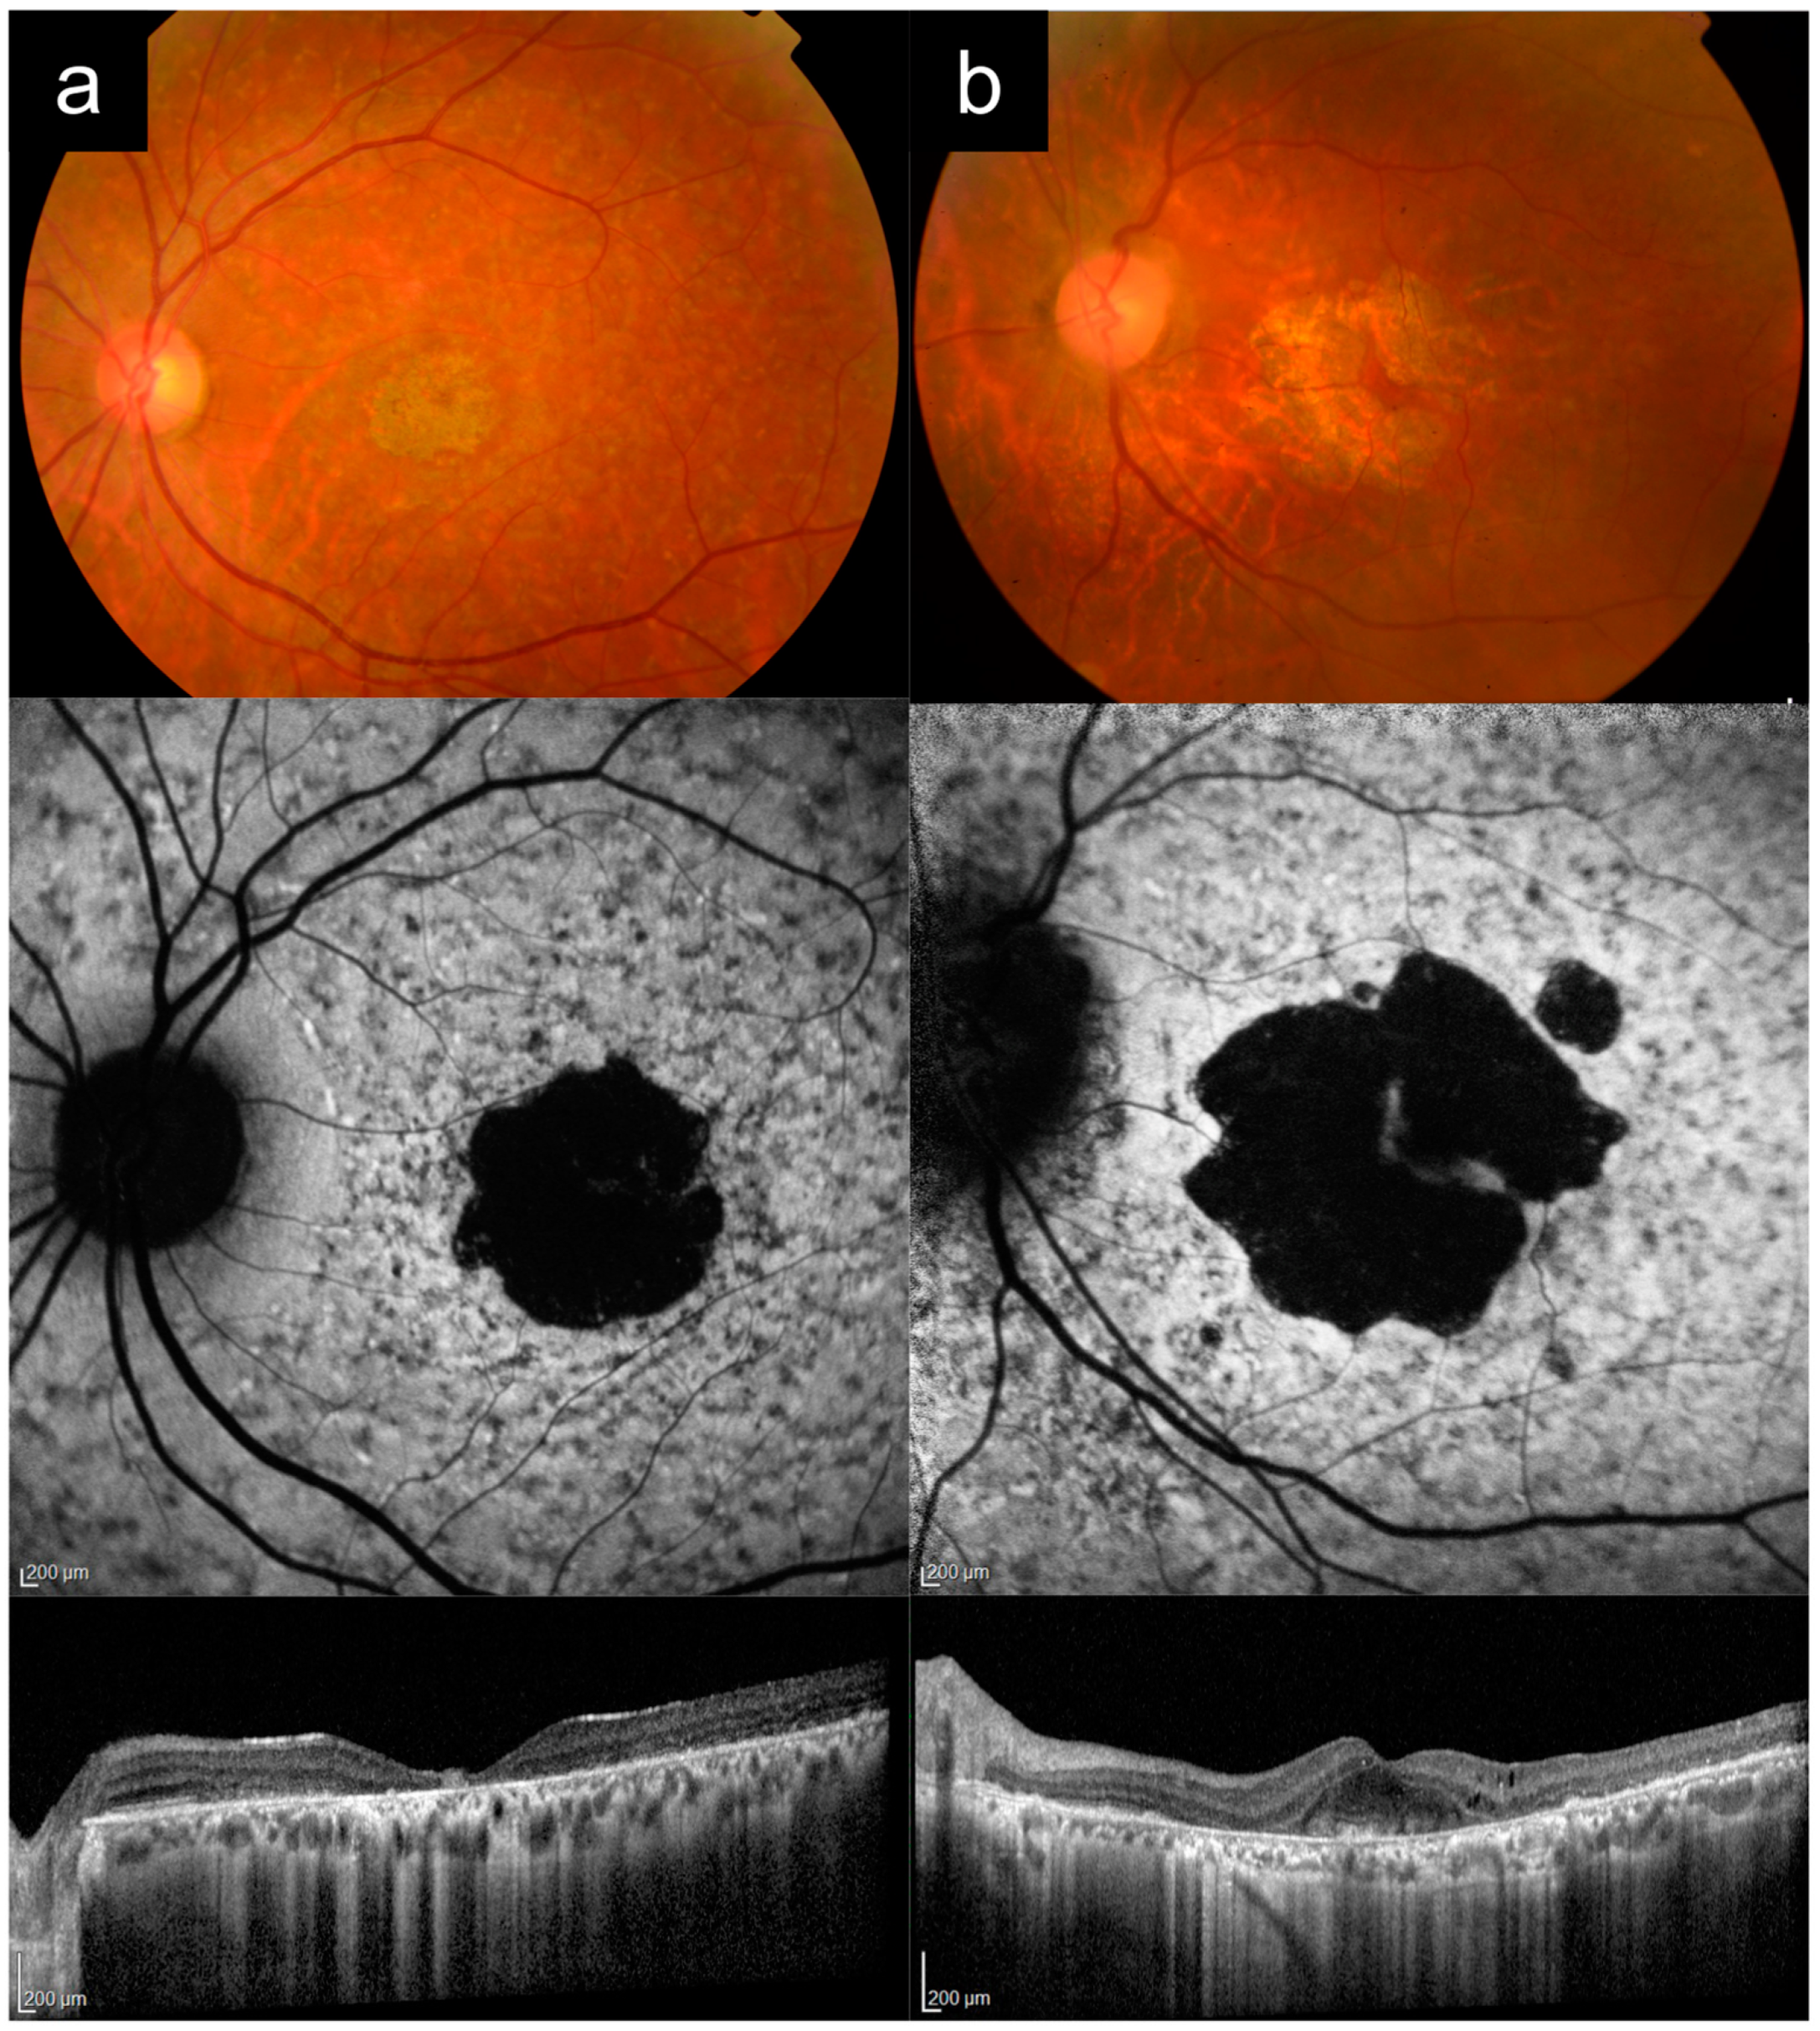

Case 1a presented with bilateral blurred central vision at 15 years of age, which progressively worsened over time. There were no other affected family members, consistent with autosomal recessive (AR) inheritance. Figure 1a shows multimodal imaging from when the patient was in his 30s. VA in the left eye at that time was 6/45. Fundus examination and CFP imaging showed an area of foveal retinal pigment epithelium (RPE) atrophy with a granular appearance and metallic sheen, surrounded by yellow pisciform flecks distributed throughout the posterior pole and out to the mid-peripheral retina. AF imaging showed a central geographic patch of hypo-AF surrounded by flecks with mixed hyper- and hypo-AF signal. Note the typical sparing of the peripapillary retina, which is more obvious on AF imaging, but also visible on CFP, albeit more subtle. OCT imaging showed outer retinal atrophy and ellipsoid zone (EZ) loss, with patchy choroidal hypertransmission, again with notable peripapillary sparing. Genetic testing revealed two likely pathogenic ABCA4 variants in this individual (Table 1).

Case 1b presented with complaints of persistent blurred vision and mild metamorphopsia in the left eye after uneventful cataract surgery in his late 60s. Best-corrected VA (BCVA) by manifest refraction was 6/7.5. Figure 1b shows imaging from this time, after his cataract surgery. CFP imaging showed a broad annulus of perifoveal RPE atrophy, with sparing of a small foveal island (explaining the good vision). In the rest of the macula, there were areas of subtle RPE atrophic change, but no frank flecks or yellow subretinal deposits. AF imaging, however, revealed much more apparent fleck-like lesions, although there was no peripapillary sparing. OCT imaging showed perifoveal RPE and outer retinal atrophy, with relative sparing of a small subfoveal region. Prior to genetic testing results, this patient had been diagnosed by multiple specialists as having “late onset Stargardt disease”. Genetic testing subsequently identified the PRPH2 c.533A>G p.Q178R variant. Pedigree by history revealed that the subject’s mother was also likely affected, which was consistent with an autosomal-dominant (AD) pattern of inheritance.

Case 1a represents a typical phenotype of ABCA4-RD, presenting with adolescent-onset “classical” Stargardt disease with macular atrophy, flecks, and peripapillary sparing [16,24,25]. Case 1b is a PRPH2-associated macular dystrophy mimicking Stargardt disease. Key distinguishing features between these two cases are the age of onset, peripapillary sparing, and the inheritance pattern from the pedigree (Table 2). The younger age of onset in adolescence, presence of clear peripapillary sparing, and the AR inheritance pattern all favor a diagnosis of ABCA4-RD versus PRPH2-RD. Note that the yellow deposits or flecks and AF appearance can look very similar in both diseases, as in this case. In addition, the small area of central foveal sparing in Case 1b, though absent in this Case 1a, can also occur in ABCA4-RD, as in Case 4a later.

Figure 1. Cases 1a versus 1b: Typical adolescent-onset Stargardt disease with macular atrophy, flecks and peripapillary sparing (a) versus PRPH2-associated macular dystrophy (b). Note the similar appearance on autofluorescence imaging, except for the peripapillary sparing, which is present in Case 1a, but absent in Case 1b. These cases can also be distinguished clinically based on age of onset and inheritance patterns.